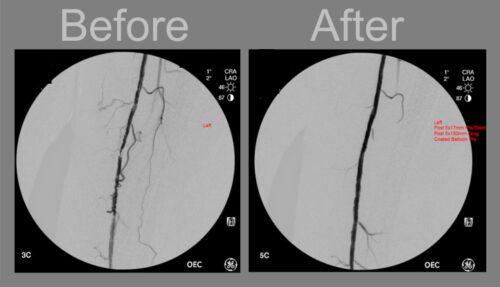

آنژیوپلاستی یک روش درمانی برای باز کردن رگ‌های مسدودشده یا تنگ‌شده قلب است. در این روش، پزشک با استفاده از کاتتر، یک بالون کوچک یا استنت (لوله مشبک فلزی) را در محل انسداد قرار می‌دهد. بالون با فشار منبسط شده و پلاک‌های رسوب‌کرده را به دیواره رگ می‌چسباند و باعث باز شدن مسیر جریان خون می‌شود.

4. بالون در محل انسداد باد می‌شود و پلاک‌ها را به دیواره رگ می‌چسباند. در صورت نیاز، استنت در رگ قرار داده می‌شود تا مسیر جریان خون باز بماند.

بله، پزشکان برای تشخیص انسداد عروق ابتدا آنژیوگرافی را انجام می‌دهند. در صورتی که انسداد مشخص شود، می‌توان آنژیوپلاستی را بلافاصله پس از آنژیوگرافی انجام داد. این فرآیند هم‌زمان که به عنوان مداخله کرونری از راه پوست (PCI) نیز شناخته می‌شود، در بسیاری از موارد برای بازگرداندن جریان خون و بهبود علائم بیماری عروق کرونری استفاده می‌شود.